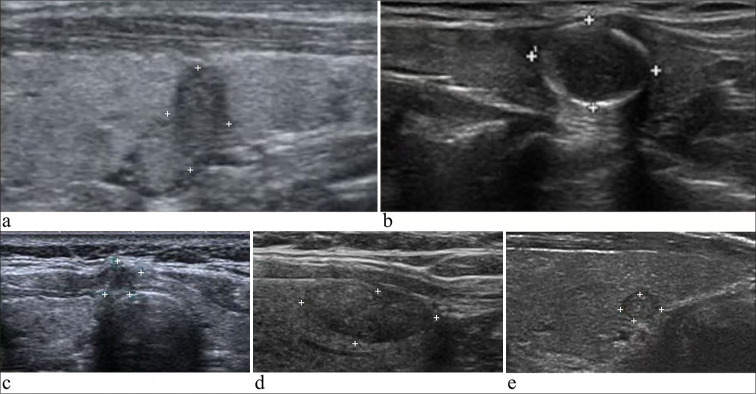

Material and methods: The clinical data of patients with thyroid nodules, suspicious of malignancy at ultrasound (US), who underwent US-guided FNAC between December 2020 and March 2023 at our cancer center were reviewed. Patients with an indeterminate diagnosis, that is, conflicting results of the BSRTC and BRAF mutation status after FNAC, were enrolled. The following four combinations of BSRTC and BRAF mutation status were considered indeterminate: (1) Group 1, BSRTC I and positive for a BRAF mutation; (2) Group 2, BSRTC II and positive for a BRAF mutation; (3) Group 3, BSRTC III and positive for a BRAF mutation; and (4) Group 4, BSRTC V and negative for a BRAF mutation. Finally, only patients who underwent surgical treatment at our center were included in the data analysis.

Results: Among the 1,044 eligible patients, 687 underwent surgical treatment. Of the 687 patients, 117 were in Group 1, 14 in Group 2, 394 in Group 3, and 162 in Group 4. Histopathological examination showed that 677 (98.5%) patients had papillary thyroid cancer, including 585 with papillary thyroid microcarcinoma, whereas only 10 (1.5%) had benign nodules. The malignancy rates were 98.3%, 100%, 98.7%, and 98.1% for Groups 1 to 4, respectively. Among the 387 patients in category 4A by the thyroid imaging reporting and data system (TI-RADS 4A) through the US, the malignancy rate was 98.4%, and for the 116 nodules <5 mm in diameter in the US, the malignancy rate was 99.1%. When combining TI-RADS 4A and a nodule diameter <5 mm, the malignancy rate was 98.9% (88/89). A total of 179 patients (26.1%) had histopathologically confirmed central cervical lymph node metastasis, and 46 (6.8%) had lateral cervical lymph node metastasis. Two nodules in Group 1, five nodules in Group 3, and three nodules in Group 4 were determined to be benign post-surgery. The benign thyroid nodules included seven dysplastic, one adenomatous, one fibrotic, and one hyperplastic.